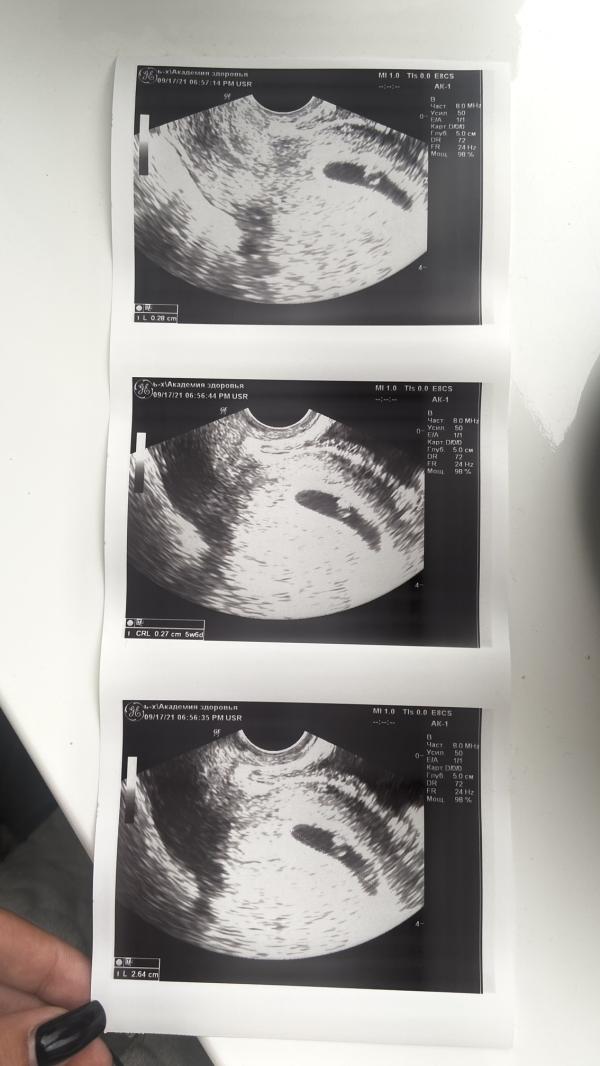

Первое узи) 5,6 недель ☺️☺️☺️

Уже бьется сердечко 155 ударов в минуту) желточный мешочек 2,8мм а плодное яйцо 26мм😍